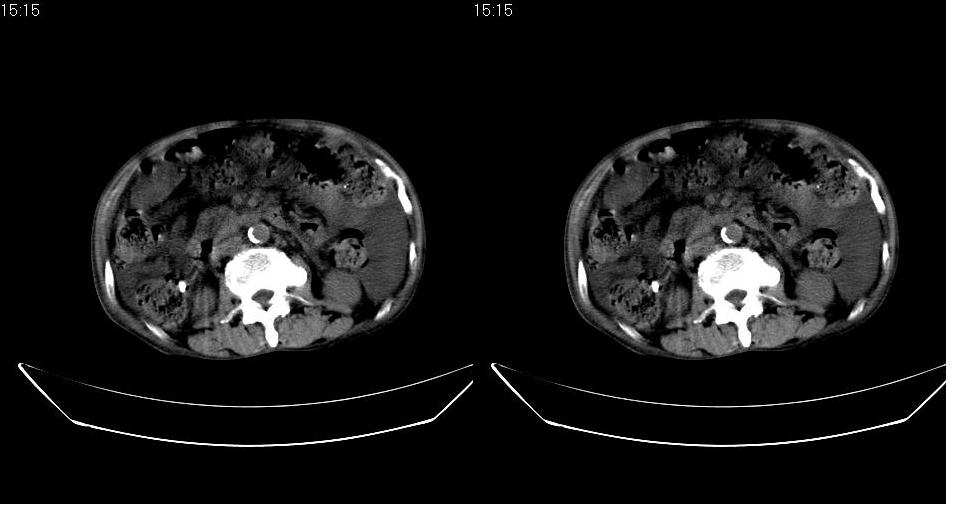

男 78岁,全身黄染,病人家属拒绝增强。

胆总管下端梗阻(原因待查)伴肝内外胆管扩张、胆囊积水。

肝周 脾周 胆囊窝内明显积液,胆囊扩大,胆囊壁模糊,肝内胆管扩张。考虑;胆囊癌周边侵润伴腹水。

1、梗阻性黄疸(胆总管下段病变或十二指肠病变)。

2、胆囊炎,腹水。

3、肝内钙化灶(寄生虫?)。